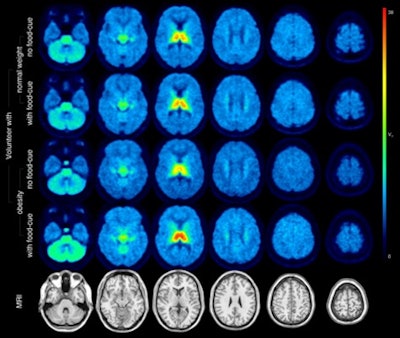

The group enrolled 15 people with obesity (average body mass index [BMI], 38 +/- 3 kg/m2) and 16 normal-weight people for PET/MRI scans with F-18 flubatine, a radiotracer developed more than 20 years ago to bind to a4b2 receptors. Participants underwent hybrid PET/MRI twice on separate days, once while in a resting state and once under "food cue stimulation" -- the subjects were shown food pictures just prior to the scans, Hesse said.

In the resting state, no significant difference in total distribution volume of F-18 flubatine was noted between the groups. However, while viewing photos of food, the total distribution volumes (VT) of F-18 flubatine was higher in obese subjects in the brain's thalamus region where a4b2 receptors are located compared to the control group (28.8 ± 2.1 vs. 25.1 ± 1.9, p = 0.03), according to the findings.